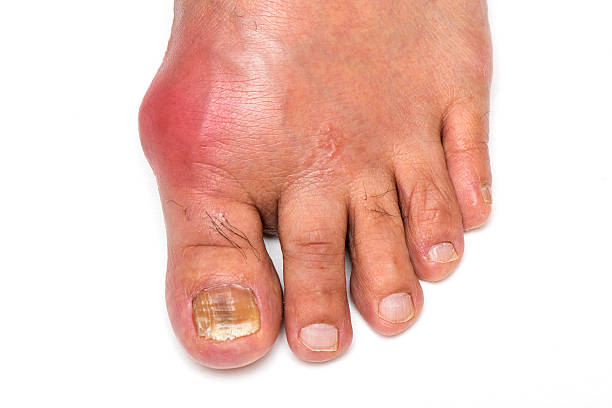

발적

발적 부위는 붉고 따끔거리며, 적출물로 인해 부어오를 수 있습니다. 이러한 발적은 대개 발작이 발생하는 부위에 나타나며, 발적이 심한 경우 걷는 것이 어려울 수 있습니다.

통풍은 대개 발적을 침범하며, 발적 주위의 관절에서도 통증을 일으킬 수 있습니다. 대개 발목, 무릎, 발가락 등을 포함하며, 통증은 심할 때 걷는 것이 거의 불가능할 정도로 심해질 수 있습니다.